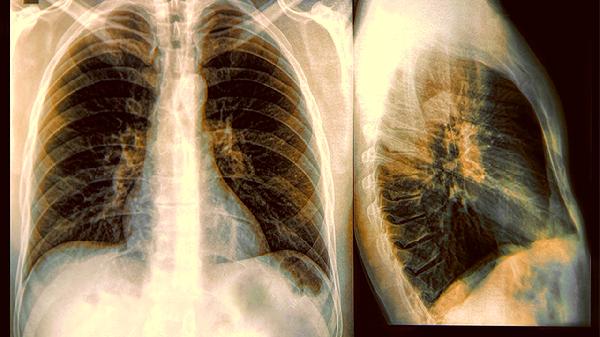

肺癌不是突然来的?医生提醒:吃饭出现这2个异常,一定不要拖着